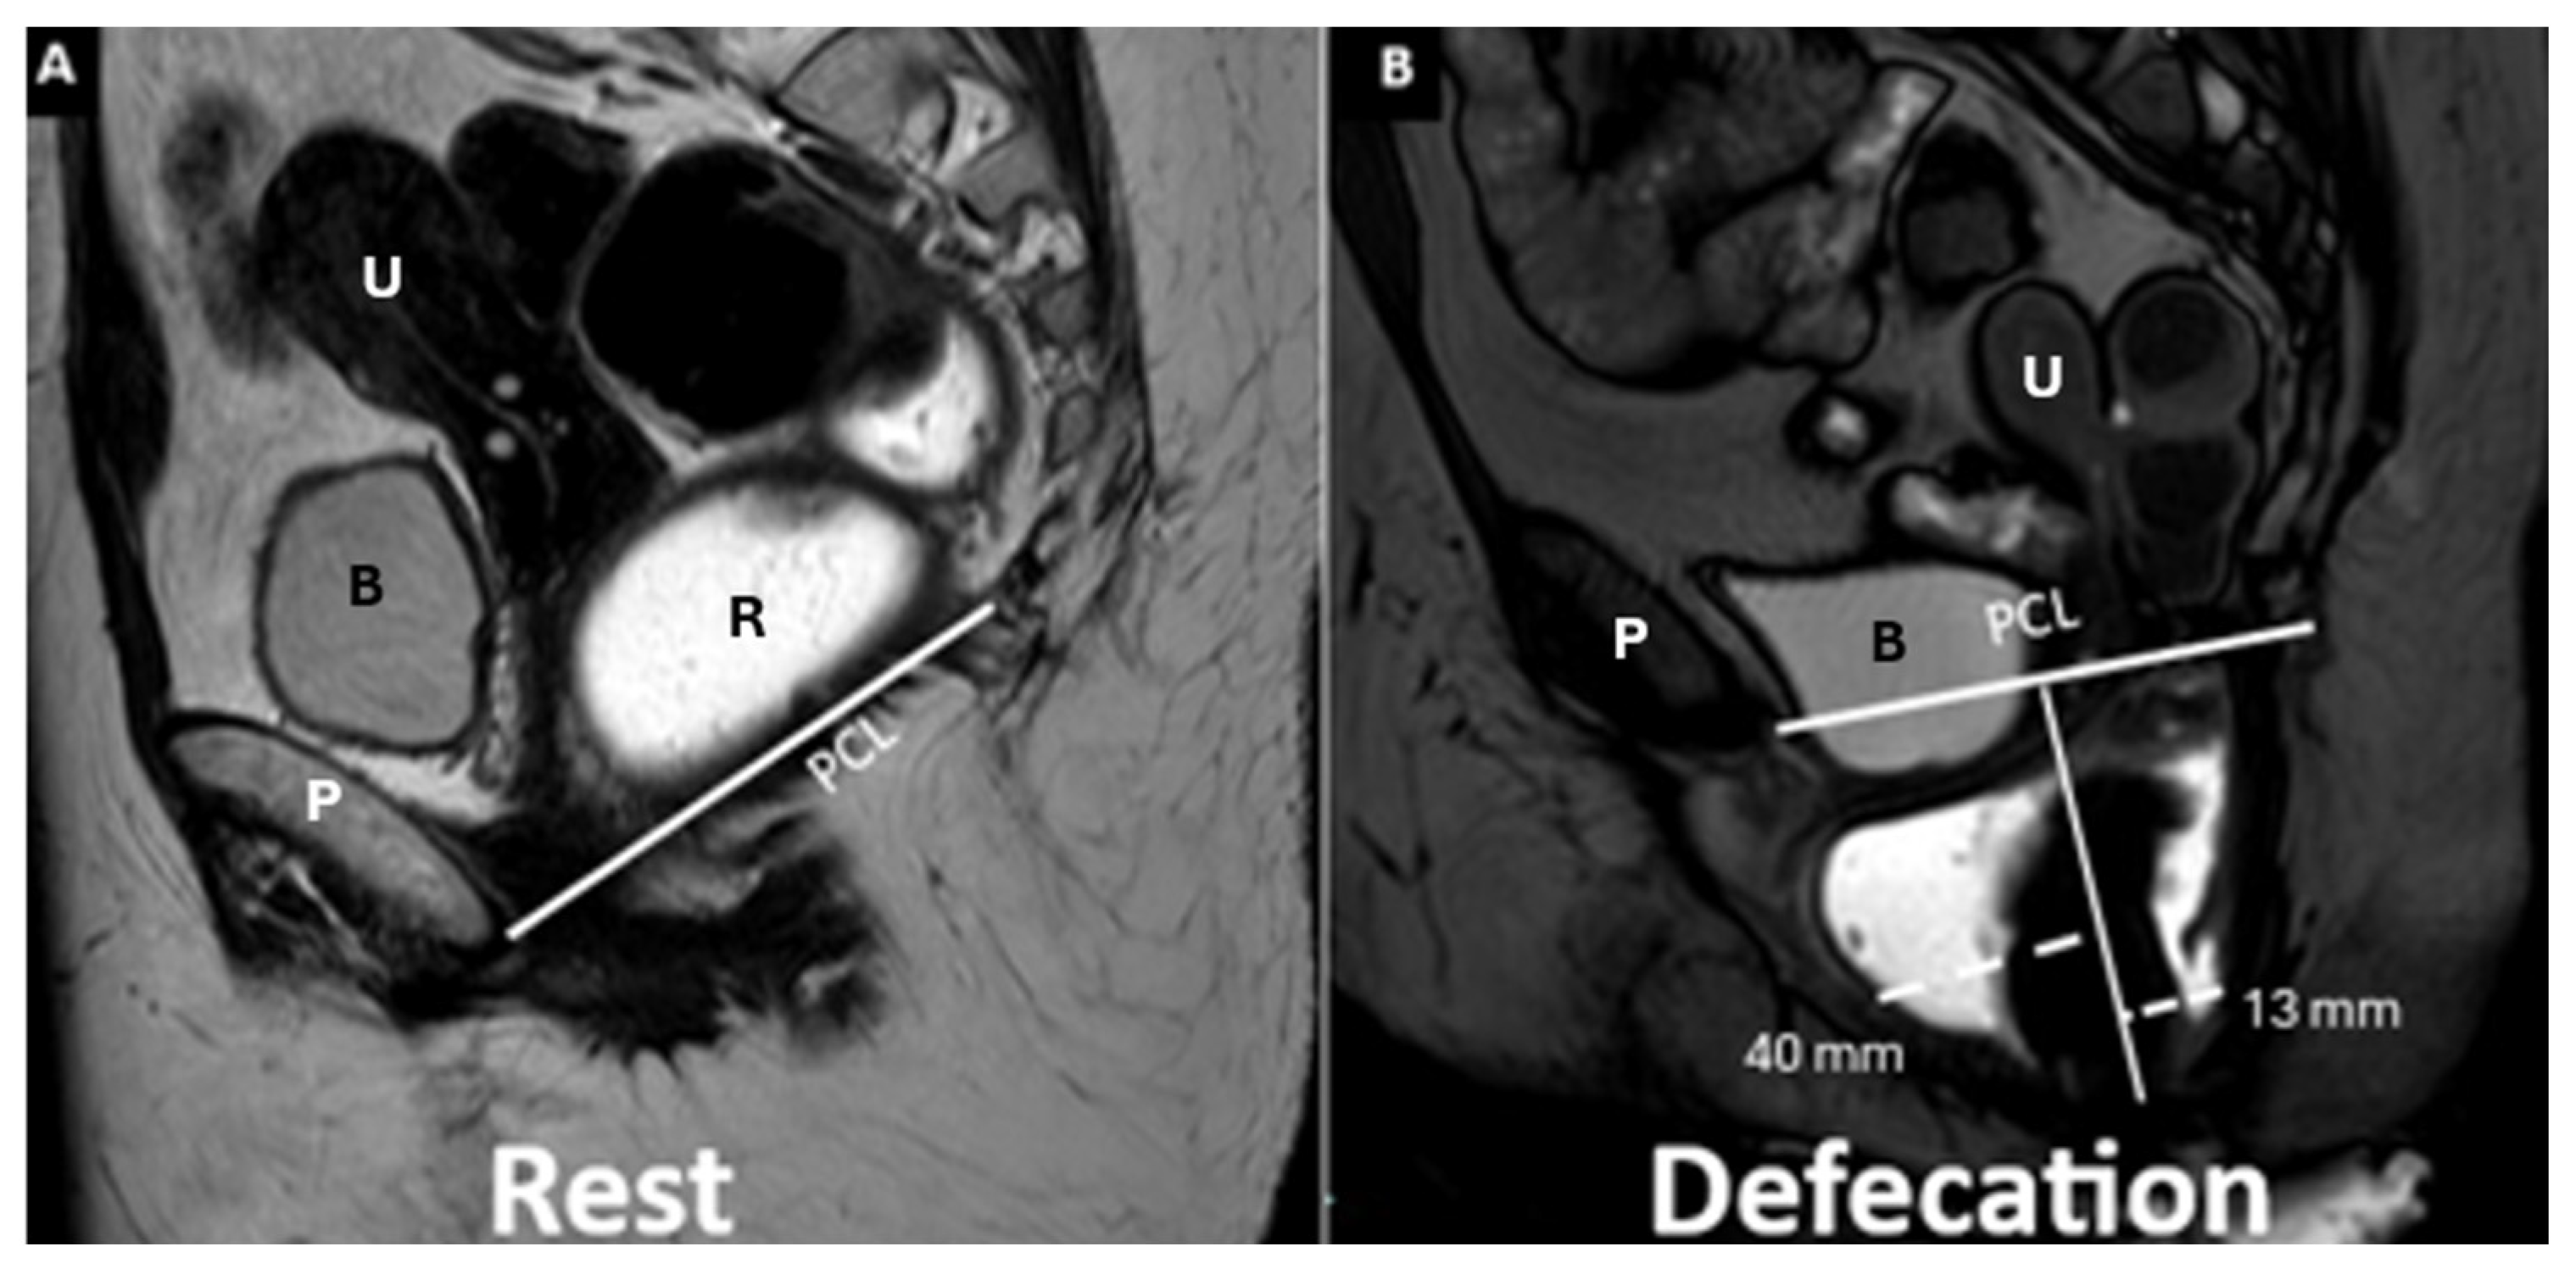

| Pubococcygeal Line (PCL) | Line from the inferior pubic border to the last coccygeal joint | Baseline for measuring organ descent | PCL Compartment Staging Stage 0: Above PCL Stage I: Descent <3 cm below PCL Stage II: Descent 3–6 cm below PCL Stage III: Descent >6 cm below PCL Stage IV: Complete organ prolapse |

Cystoceles